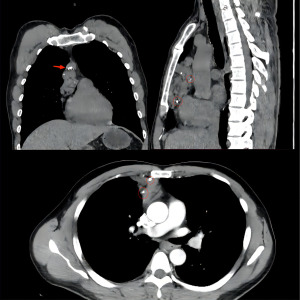

A 40-year-old patient underwent chest computed tomography (CT) during a routine medical examination, and an anterior mediastinal mass was detected. The patient had undergone fracture fixation one year earlier for a right calcaneal fracture, and the internal fixation in the calcaneus was not removed. Otherwise, the patient had no other past medical history, his physical examination and laboratory data were normal, he had no history of chronic or genetic disease, and a chest radiograph showed no abnormalities. A CT scan revealed that a mediastinal mass was located in the anterior mediastinum. The mass range was approximately 9.2 cm × 3.9 cm × 3.6 cm. The CT scan also showed that the mass had a smooth surface and heterogeneous contents. The upper border of the tumour was from the sternal angle and the inferior border of the tumour was at the aortic outflow. The contrast-enhanced CT scan revealed uneven delayed enhancement shadows with multiple punctate calcifications (Figure 1). The patient was unable to undergo magnetic resonance imaging (MRI) due to the internal fixation in the right calcaneus. According to preoperative examinations and imaging reports, we suspected that the mass in the anterior mediastinum was a haemangioma. Mediastinal haemangiomas require differentiation from mediastinal cysts, neurogenic tumours, teratomas, and lymphomas. For diagnosis and treatment, we performed a minimally invasive thoracoscopic mediastinal tumour resection and sent the resected tumour for postoperative pathological examination. After the patient received general anaesthesia and a double lumen endotracheal tube was placed, we introduced a thoracoscope using a trocar in the seventh intercostal space at the posterior axillary line. We placed two other working trocars in the third and sixth intercostal spaces at the anterior axillary line in order to insert the dissecting instruments. The mass was located in the anterior mediastinum encased in a vascular cluster (Figure 2). We opened the mediastinal pleura with an electrocoagulation hook, and the anterior mediastinal haemangioma was resected along the mediastinal adipose tissue. We found that the tumour adhered closely to the superficial pericardium vessels and likely served as a source of vascular supply for the tumour; therefore, these vessels were carefully removed by dissection and the total thoracoscopic resection of the suspected mediastinal haemangioma was complete.

Mediastinal haemangioma is often nonspecific on X-ray and CT imaging. The chest X-ray showed that the haemangioma was a round or lobulated mass. The presence of phleboliths in the lesion was found to be diagnostic, since this feature appears in 10% of patients with mediastinal haemangiomas (3). Moreover, thrombus in the haemangioma, venous inflammation and calcification form phleboliths that appear as rings or spotty calcifications on chest radiography. If the haemangioma is adjacent to the ribs, manifestations of erosion are observed in the ribs. Malignant mediastinal haemangiomas, which show ill-defined and peripheral invasion, can also erode the chest wall. A haemangioma typically appears as a heterogeneous lesion on an unenhanced CT scan, while the degree of internal enhancement of mediastinal haemangioma is heterogeneous on examination with contrast-enhanced chest CT. The degree of central enhancement is significantly higher than that at the edge, which may be a specific manifestation of haemangioma (9). Significant draining veins with local dilatation or venous aneurysm can be found on contrast-enhanced CT. The walls of the draining veins and feeding arteries in the lesion are smooth and regular, which may help to identify other blood-rich malignant tumours that are invading the blurred and irregular vascular wall. Blood supply arteries and draining veins are the main factors that increase the significant risk of bleeding and blood loss (10), and preoperative contrast-enhanced CT reveals draining veins, which are very important for surgical planning. In this case, the feeding artery and drainage vein of the haemangioma were clearly visible by preoperative chest enhanced CT, which allowed thoracoscopic surgery to proceed smoothly.